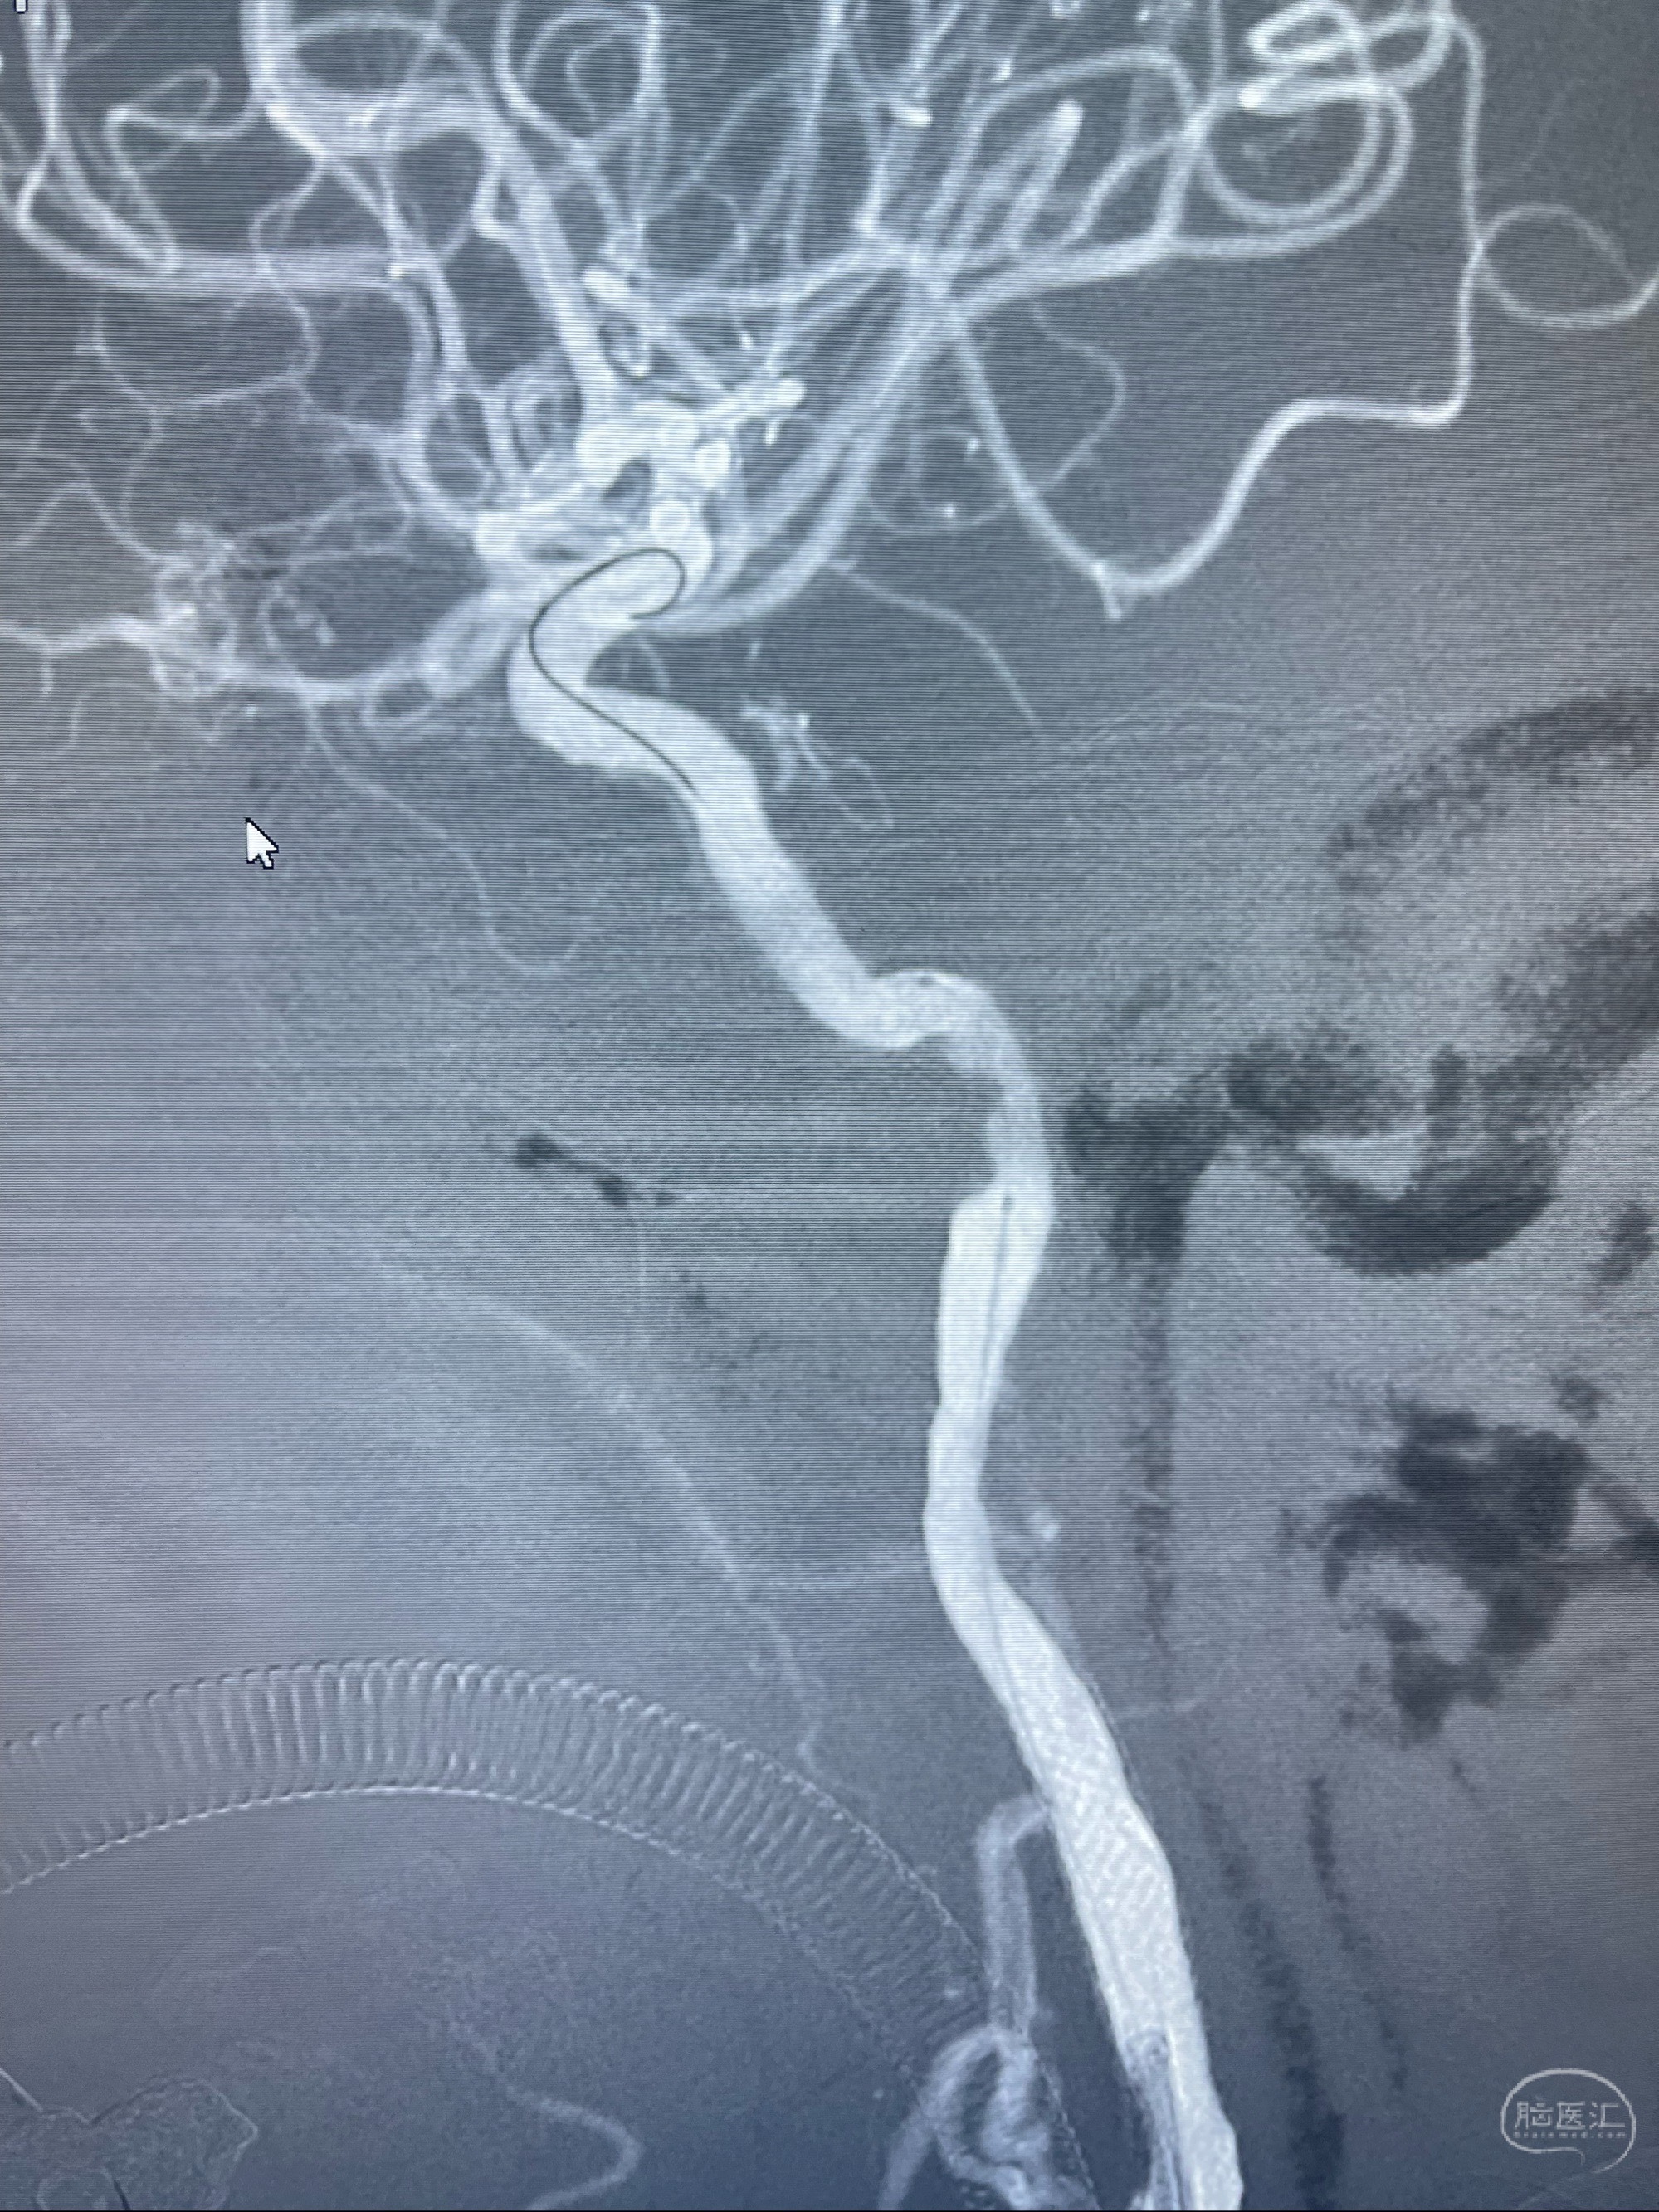

2023-07-10DSA:右侧颈内动脉岩骨段夹层伴中偏重度狭窄改变,左侧颈总动脉闭塞、右侧颈外动脉由右侧肋颈干甲颈干吻合代偿

箭头所示为颈内动脉岩骨段重度狭窄,结合MRI,考虑为肿瘤侵犯右侧颈内动脉

箭头以近至支架段管腔不规则狭窄